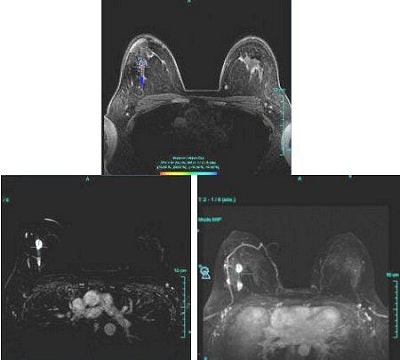

Time-intensity curves were performed with CAD on the right breast lesions at the 10 o'clock position, 3 cm and 4 cm from the nipple (figure 1 and figure 2, respectively, below). Dr. Christiane Kuhl and colleagues described three basic time-intensity curve types as summarized in table 4. A graphic illustration of the various curves is presented in figure 3 (Radiology, April 1999, Vol. 211:1, pp. 101-110).

| Figure 1: Type III curve (below) corresponding to the right breast lesion at the 10 o'clock position, 3 cm from the nipple (above). All images courtesy of Dr. Kathleen Klaas and Bernadette Kaufman. |

Figure 1 demonstrates a type III curve corresponding to the right breast lesion at the 10 o'clock position, 3 cm from the nipple. In observing the parametric map and subtraction image, the enhancement pattern is suspicious for malignancy. A rapid uptake of contrast is immediately followed by rapid washout. Figure 2 shows similar tissue kinetics for the lesion 4 cm from the nipple.